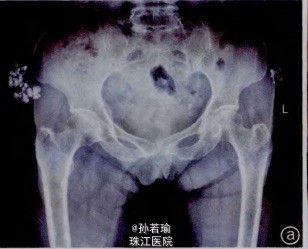

患者,女,78岁,双髂部疼痛,不能侧卧1个月。无发热、消瘦乏力,无外伤史。于我院门诊行X线检查提示:双髂骨外侧高密度钙化影,边界清(间图1a)。

体温:36.5,脉搏75次/min,呼吸18次/min,血压130/80mmHg.全身浅表淋巴结无肿大,心肺腹未见异常。双髂部各扪及一约8cm*6cm包快,包快性质硬、不光滑,与皮肤粘连、不随髋关节活动而活动(见图1b),局部皮温不高,轻压痛。血常规、血糖、肝肾功能、血钙、尿酸等实验室检查结果均正常。

诊断:双髂部巨大瘤样钙盐沉积症TC 择期在蛛网膜下腔阻滞麻醉下行肿物探查切除术。术中见肿物位于双髂部皮下,呈圆饼状,均8cm×6cm大小,无囊壁包裹、与肌肉无粘连,其内为乳白色糊状钙化组织(图1c)。彻底切除肿物。刮净、止血、冲洗,采取渔网状全层缝合法闭合创面(见图2、图3),手术切口一期愈合,术后恢复良好。病例报告:肉眼可见坚硬的钙化肿块,可侵及肌腱和肌肉,其内有白色或黄白色颗粒样物质;镜下可见无定形或颗粒状的钙盐沉积,周围被致密结缔组织包绕(见图1d)。